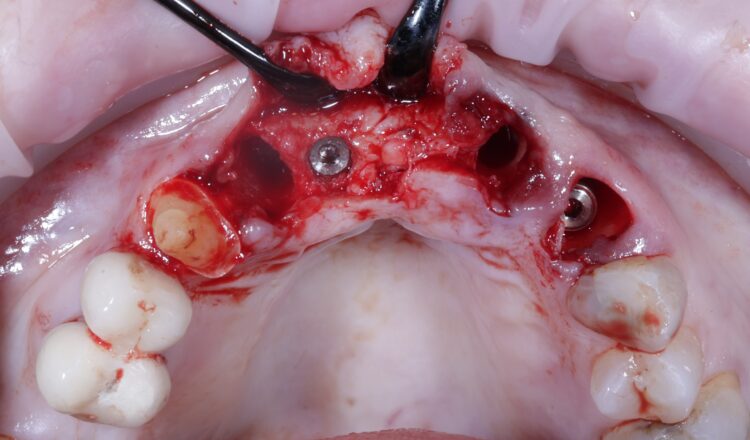

A miniflap was raised in the upper central region for this case to enhance visualisation for implant placement and augmentation. The guide was placed in the mouth and the standard guided surgery drilling protocols were followed. The new surgical kit improves workflow and intraoperative efficiency with the removal of spoons and a guide adaptor allowing for both guided and freehand use. During this step of the procedure, the guide was temporarily removed to double check the drilling angulation and verify this lined up with the pre-fabricated temporary bridge.

The two 3.3mm diameter Tapered Pro Conical implants were then placed through the guide at the pre-determined positions, angles and depths. Both implants achieved an insertion torque above 30Ncm.

Bone grafting was then performed, placing MinerOss X (BioHorizons Camlog) into the extraction sockets and the jump gap around the implant in the UL3 socket, to preserve the existing bone of the socket. This would help to minimise changes in the bone post-surgery and help to maintain the buccal profile of the ridge. The biomaterial is a bovine bone mineral matrix that has been proven to increase vertical bone height alongside implant placement.[vi] It has worked very well in my cases to date, offering a high turnover to bone for maximum stability and efficient results with immediate implant protocols.

A soft tissue graft was then performed, harvesting connective tissue from the palate and placing it in the sulcus of the UL3.

Non-engaging cylinders were placed onto the implants to connect to the pre-fabricated temporary bridge. A premade temporary bridge was connected, contoured and polished, with particular attention paid to the contour of the restoration and suturing with the aim of prosthetically guided soft tissue healing.